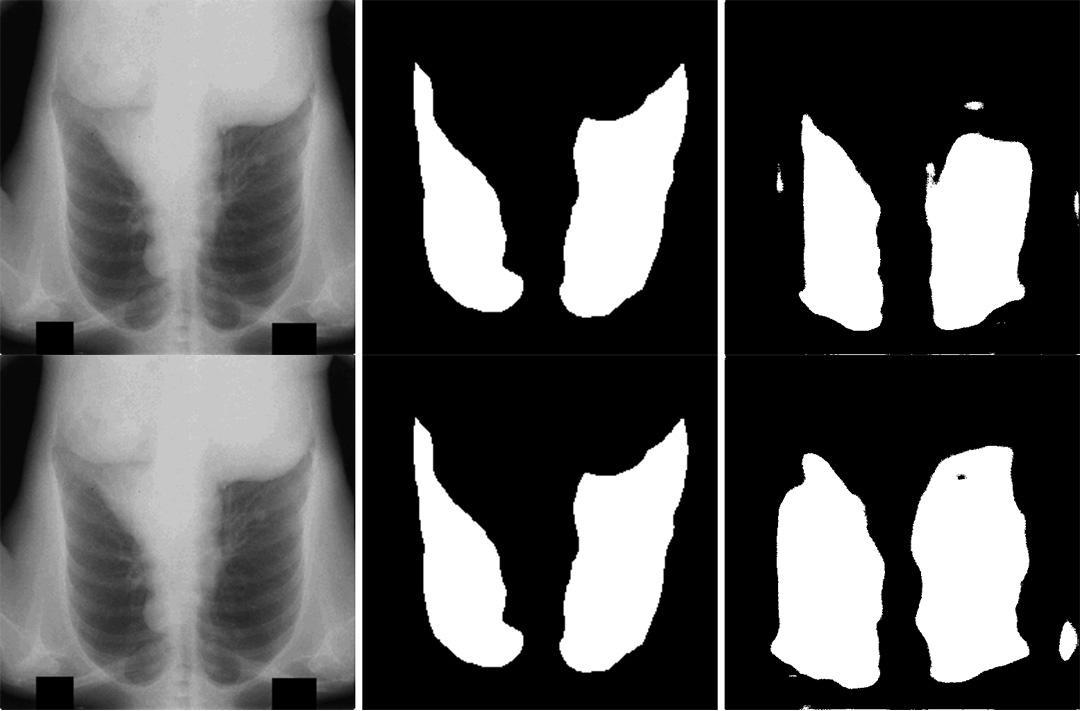

This performance of multi-stage transfer learning (MSTL) on a lung segmentation task within adverse conditions was investigated. It was concluded that most of the retrained models likely experienced covariate shifts with the exception of models trained on flipped datasets. This investigation gives insight into the thresholds of models trained on small datasets to perform under adverse conditions, adding to the knowledge base required to successfully integrate deep learning (DL) into the medical workflow.